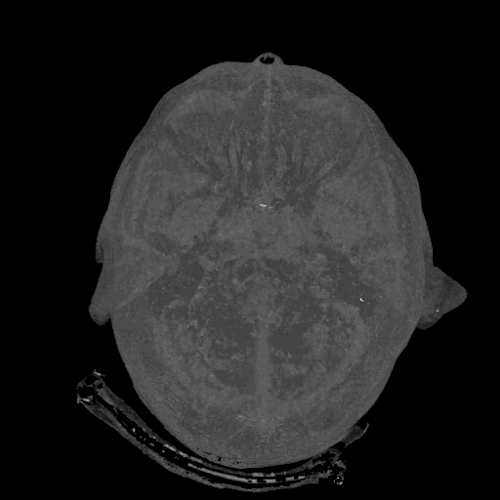

1. Bộ não của bạn là ổ đĩa flash lớn nhất trên thế giới

Bộ nhớ của bộ não có đủ dung lượng để lưu trữ 2,5 triệu GB thông tin tương đương khoảng 300 năm video. Đỉnh cao của bộ nhớ là lúc 25 tuổi và bắt đầu giảm ở tuổi 50 trừ khi bạn thường xuyên kích thích, nuôi dưỡng bộ nhớ.